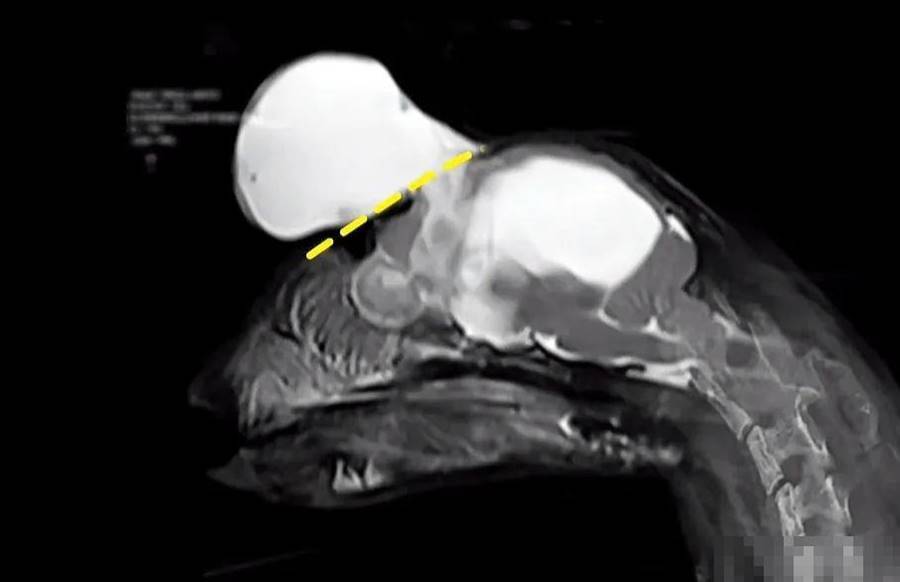

隨著身體的成長頭上的腫塊也跟著一起長大,大包開始慢慢壓住豆包的眼睛,醫生;摸了摸豆包的小腦袋,發現它腦袋上的腫塊是軟的就像氣球一樣,正常的頭骨應該完全包裹住大腦,但很明顯這個腫塊長在頭骨之外,為了準確診斷,貓咪接受了詳細的檢查,結果顯示小貓患有腦疏松癥,由于大腦內部充滿了水并在腦中產生了壓力,貓咪圓形的小腦被異常的水壓擠出了頭骨,從而在外部形成了一個軟軟的大腫塊。

實際上這也是腦組織的一部分,盡管小貓的大腦結構異常,但目前看起來完全沒有問題,值得慶幸的是由于頭蓋骨有個洞,這才導致小腦沒有破裂,醫生認為這是個醫學奇跡,如果豆包頭上沒有那個大腫塊,那它可能已經去了喵星,但問題是目前小貓只有三個月大,頭上的腫塊還會伴隨它繼續生長,這可能會導致它無法保持身體的平衡,或者引發癲癇,由于這種病例十分罕見,醫生們展開了緊急會診,最終決定再觀察一段時間,因為現在進行手術將會面臨巨大的風險。